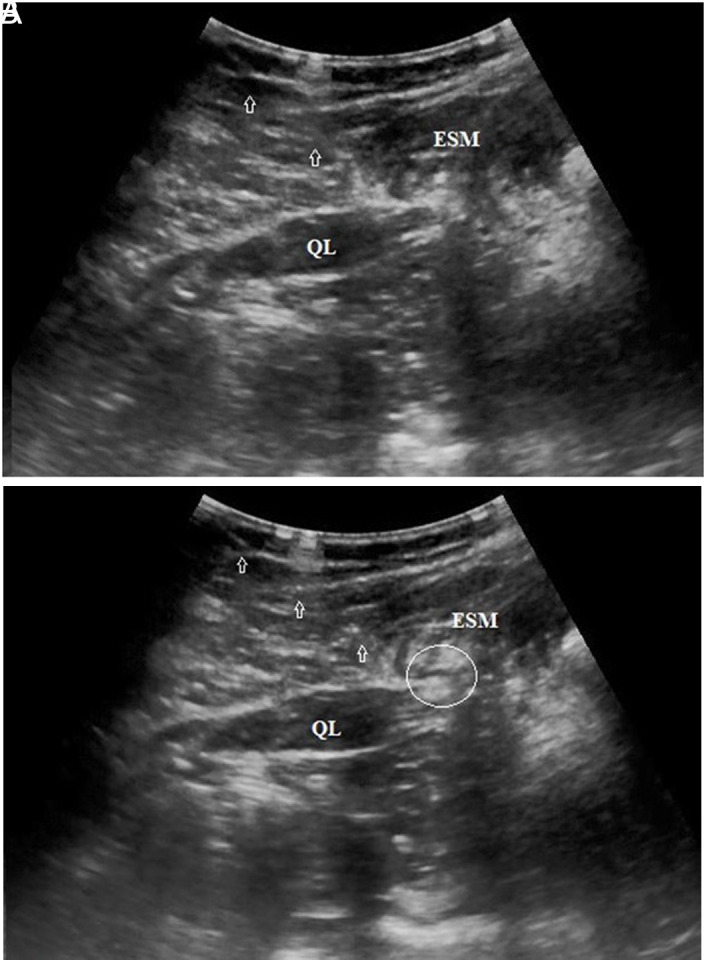

Methods:  Sixty participants with chronic LBP were recruited for this study. The patients were allocated to 2 groups: physical therapy (PT) (n=30) and PT+interfascial injection (IFI) (n=31, 10mL (0.25% bupivacaine)+methylprednisolone (40 mg) injection into the middle layer between the quadratus lumborum and erector spinae muscle). Outcome measures involved performing Numeric Rating Scale (NRS) and Oswestry Disability Index (ODI) scoring on study participants at pretreatment (PRT), as well as posttreatment at months first, second, fourth, and sixth.

Conclusion:  The study result shows that IFI applied to the middle layer of the thoracolumbar fascia may be efective in individuals with chronic LBP. The efect of fascial structures on LBP should be further investigated.